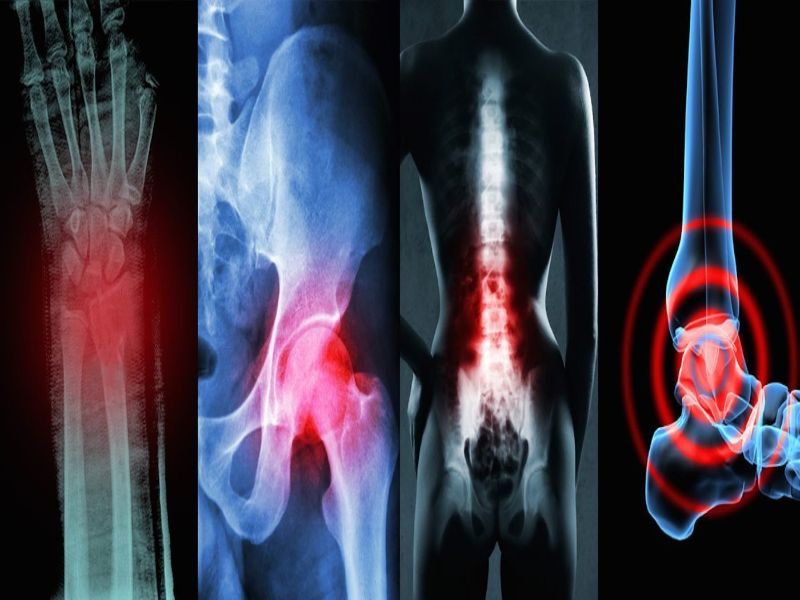

Cuando algunos de estos cartílagos sufren alguna lesión, se genera dolor, rigidez y sobre todo incapacidad funcional. Comúnmente la artrosis se encuentra en la columna cervical y lumbar de los seres humanos, algunas de las veces también se pueden localizar en los hombros y los dedos de las manos. En las caderas, rodillas y rara vez en la articulación del dedo gordo del pie.

Los tipos de artrosis dependiendo de la zona afectada en los seres humanos, se pueden mencionar las siguientes:

- Artrosis de cadera

- Artrosis cervical

- Artrosis lumbares

- Artrosis de mano

- Artrosis de rodilla